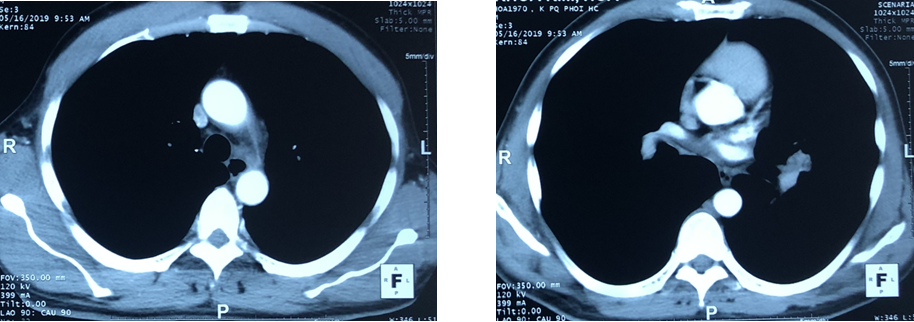

- Chụp PET/CT:

+Hình ảnh khối u phế quản gốc trái 4,6x4,3cm, maxSUV=13,84. Nốt mờ phổi phải 0,7cm, maxSUV=1,99.

+Hạch rốn phổi trải 1,9cm, maxSUV=4,59.

+Hạch trung thất trái 2,8cm, maxSUV=7,75.

Hình 1a: Hình ảnh chụp PET/CT cho thấy khối u phế quản gốc trái 4,6x4,3cm, maxSUV=13,84 (mũi tên vàng).

Hình 1b: Hình ảnh chụp PET/CT cho thấy hạch rốn phổi trải 1,9cm, maxSUV=4,59; Hạch trung thất trái 2,8cm, max SUV=7,75 (mũi tên đỏ).

Hình 1c: Hình ảnh chụp PET/CT cho thấy nốt mờ phổi phải 0,7cm, maxSUV=1,99 (mũi tên xanh).